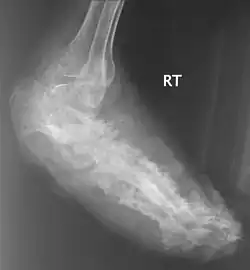

An infected foot | |

X rays and ultrasonography may be carried out to assess the extent of the disease. X rays findings are extremely variable. The disease is most often observed at an advanced stage that exhibits extensive destruction of all bones of the foot. Rarely, a single lesion may be seen in the tibia where the picture is identical with chronic osteomyelitis. Cytology of fine needle aspirate or pus from the lesion, and tissue biopsy may be undertaken sometimes.[11] Some publications have claimed a "dot in a circle sign" as a characteristic MRI feature for this condition (this feature has also been described on ultrasound).[14]